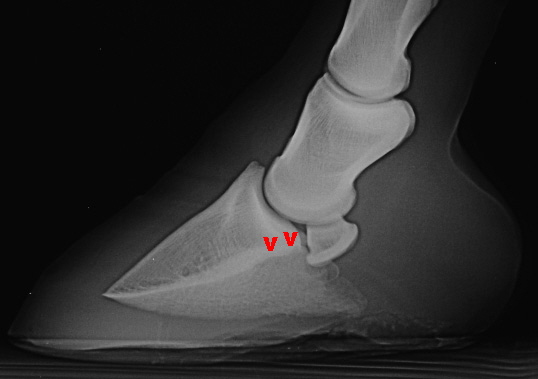

Abgesehen von der Hufgelenksarthrose (A) liegt hier eine isolierte Verkalkung im Bereich des  oberen Strahlbeinbandes (v) vor, die Gleitfläche für die tiefe Beugesehne (g) ist unruhig, der Markraum ist verdichtet (sklerosiert - s).  Kategorie IV bzw. Grad 4.